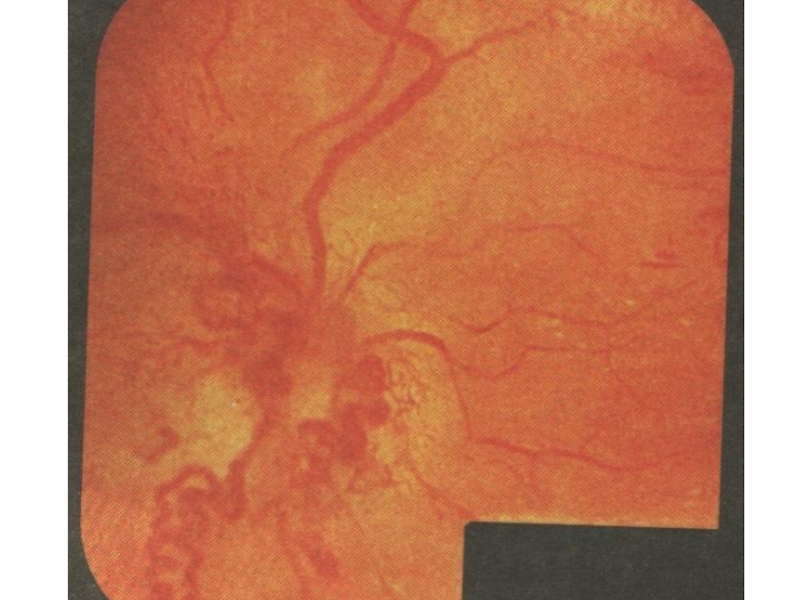

Слайд 66Офтальмоскопически:

1. картина «раздавленного помидора»;

2. ДЗН отечный, границы его стушеваны;

3. ДЗН

темно-красного цвета;

4. вены резко расширены, темные, извиты;

5. артерии узкие;

6. отек

сетчатки;

7. новообразованные сосуды, венозные анастомозы, артериовенозные шунты;

8. плазморрагии;

9. м.б. витреальные геморрагии.

Офтальмоскопически:1. картина «раздавленного помидора»;2. ДЗН отечный, границы его стушеваны;3. ДЗН темно-красного цвета;4. вены резко расширены, темные, извиты;5.